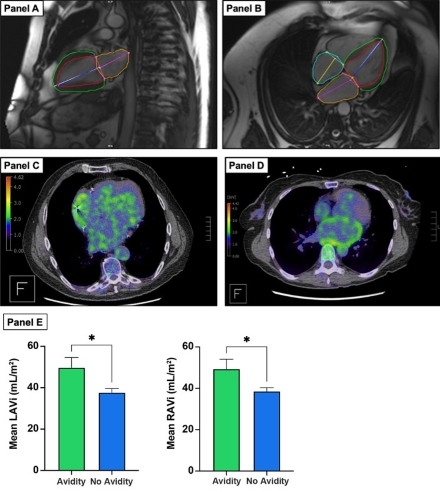

Patients undergoing FDG-PET for the evaluation of cardiac sarcoidosis (CS) were assessed for atrial avidity. Atrial FDG uptake, a semi-quantitative measure, was quantified using standardized uptake value SUV-mean, SUV-max, and normalized to the blood pool as the target-to-background ratio (TBR). Atrial volume assessment was obtained from cardiac magnetic resonance imaging (CMR) scans done prior to PET. Right atrial volume index (RAVi) was obtained from monoplanar 4 chamber view while left atrial volume index (LAVi) was obtained from biplanar method.

One hundred and fifty-eight patients (age 61 ± 15 years, 37% female, BMI 29.6 ± 6.5 kg/m2) were included in the study. CS was noted in 43 (27.2%) patients and AF in 49 (31%) patients. Regression analysis showed an association between LAVi and atrial TBRmax (β=0.005, p =0.007) but no association between RAVi and atrial TBRmax (β=0.002, CI -0.002-0.006 p =0.08) after adjustment for AF and cardiac sarcoidosis. Location specific analysis showed that RAVi was associated with right (OR 1.03, p=0.01) and biatrial uptake (OR 1.05 p=0.02). However, LAVi was only associated with biatrial uptake (OR 1.04, p=0.04). Patients with atrial avidity had a significantly higher LAVi and RAVi (46.8±21.7 vs 38.1±13.9 mL/m2, p=0.02, 44.4±18.4 vs 36.5±13.1 mL/m2, p=0.02). In AF patients specifically, this relationship remained significant with RAVi (51.5±20.6 vs 39.1±14.4 mL/m2, p=0.02) while no difference was found with respect to LAVi (54.2±23.5 vs 42.8±14.4 p=0.06).

Atrial-specific FDG uptake is associated with dilation of the corresponding chamber. This suggests that altered substrate utilization may contribute to localized atrial remodeling. Further research is needed to explore the temporal nature of this association.